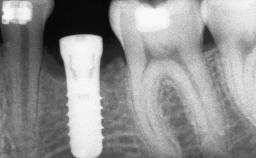

A 20-year-old woman was referred for implant therapy in 2004. Her medical history revealed no significant findings, and neither did she smoke nor take any medications. An extraoral examination revealed no abnormalities of the skin, hair or nails. The intraoral examination revealed only 11 permanent teeth clinically. These were normal in shape, size, and color. In addition, eight retained deciduous teeth (53, 62, 63, 71, 72, 73, 81, 82) were present. No abnormalities were detected during the general examination. The family history revealed that the patient’s father and two sisters were on record with similar conditions. The clinical examination revealed a thick gingival biotype. No recession of the attached gingiva was noted, but the retained deciduous teeth were mobile and unsightly. As a syndrome had not been diagnosed, the case was categorized as non-syndromic oligodontia.

Bone Volume Deficient horizontally, requiring prior grafting